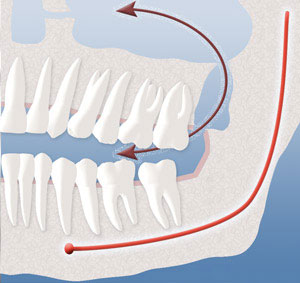

Damage to Sensory Nerve:

A primary concern is a nerve within the lower jaw bone that supplies feeling to the lower lip, chin, and tongue. This nerve is frequently very close to the roots of the lower wisdom teeth. Having these teeth out between the ages of 12 and 18 usually provides shorter roots so that the nerve is not so close to the roots of these teeth. Occasionally, when the teeth are removed, and especially in older patients, the nerve can become injured. When local anesthesia wears off, you may experience a tingling or numbing sensation in the lower lip, chin, or tongue. Should this occur, it is usually temporary and will resolve gradually over a period of weeks or months. On rare occasions it can result in a permanent alteration of sensation similar to having local anesthesia. We feel that you should be aware of this possibility before consenting to surgery.